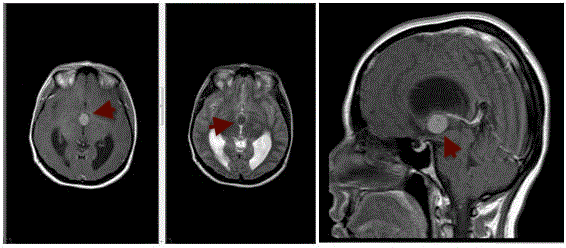

Εντοπίζεται στο πρόσθιο τμήμα της 3ης κοιλίας, στο κέντρο του εγκεφάλου, σε σημείο τπου εμποδίζει τη φυσιολογική ροή του εγκεφαλονωτιαίου υγρού.

Πρόκειται για μία κύστη, το σχήμα της οποίας θυμίζει ρόγα από σταφύλι και περιέχει ένα κολλώδες υγρό σαν βλέννη.